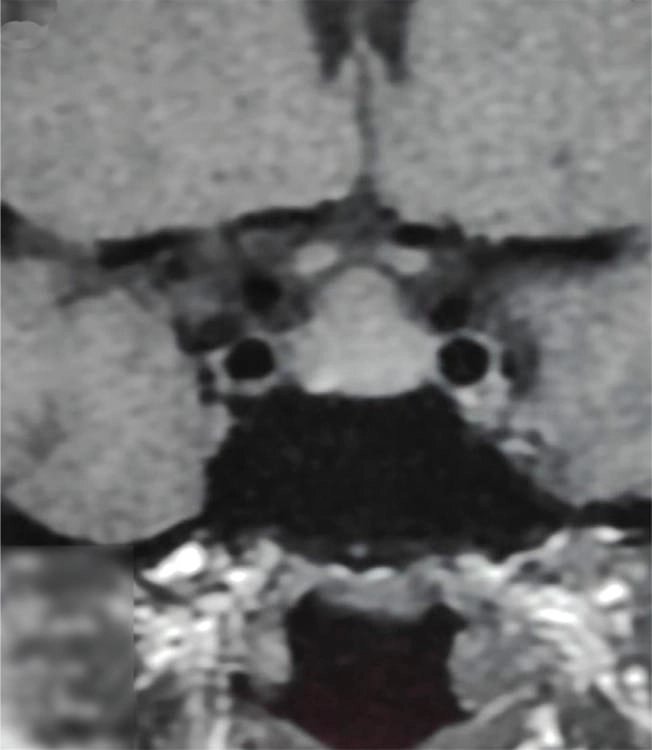

কেস ১: একজন ১৬ বছর বয়সী কিশোরী প্রাথমিক অ্যামেনোরিয়া ও খর্বাকৃতিজনিত কারণে এমআরআই করার পর একটি পিটুইটারি টিউমার শনাক্ত হয় এবং তাকে অস্ত্রোপচারের জন্য রেফার করা হয়। তবে তার রক্ত পরীক্ষায় পাওয়া যায় TSH ছিল 119.20 এবং Free T4 ছিল 4.14 pmol। এই অস্বাভাবিক মাত্রার কারণে এটিকে একটি থাইরোট্রোফ হাইপারপ্লাসিয়া হিসেবে বিবেচনা করা হয় এবং তার চিকিৎসা শুরু হয় এবং ৬ মাসের মধ্যে উচ্চতা ১২৪ থাকে বেড়ে ১৩১ সেমি হয় এবং তার ঋতু ও শুরু হয় এবং MRI-তে টিউমার সম্পূর্ণভাবে অদৃশ্য হয়ে যায়।

কেস ২: একই রকমভাবে, ১৫ বছর বয়সী আরও একজন কিশোরী অল্প উচ্চতা ও টিউমার সন্দেহে নিউরোসার্জেনের কাছে রেফার করা হয়। তার TSH ছিল 100 এবং MRI-তে একটি ডোম-আকৃতির টিউমার দেখা যায়। যাকে ওষুধের চিকিৎসায় সত্য জীবনে ফিরিয়ে আনা হয় এবং ৬ মাসে তার উচ্চতা বৃদ্ধি পায় ও নিয়মিত মাসিক শুরু হয়। MRI-তে টিউমার সম্পূর্ণ অদৃশ্য হয়ে যায়।